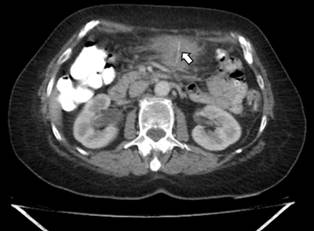

Se trata de una paciente femenina de 67 años de edad, sin antecedentes patológicos, quien ingresó al servicio de urgencias con un cuadro clínico de aproximadamente 16 días de evolución de dolor abdominal en el cuadrante superior izquierdo, escalofrío, inapetencia y pérdida de peso de aproximadamente 6 kilos. Dentro de los estudios practicados, inicialmente se tomó una endoscopia digestiva alta, en la que se evidenció una lesión en la vertiente extrínseca de curvatura mayor, con sospecha de lesión subepitelial frente a la compresión extrínseca de 5 cm, con mucosa adyacente normal, ecografía de abdomen, imágenes de engrosamiento de la cama gástrica con imágenes ecogénicas que invaden la luz y sombra acústica posterior, colonoscopia con reporte de diverticulosis y sospecha de tumor sobreinfectado, por lo cual se realizó una tomografía axial computarizada (TAC) de abdomen y se encontró una masa exofitica con densidad de tejidos blandos que se localiza en relación con la curvatura mayor del estómago, aparentemente sólida. Las posibilidades diagnósticas a considerar son tumores del estroma gastrointestinal (GIST gástrico) frente a la reacción al cuerpo extraño (Figura 1). Los marcadores tumorales fueron negativos; el hemograma resultó sin leucocitosis, sin anemia y con PCR elevada (172,9).